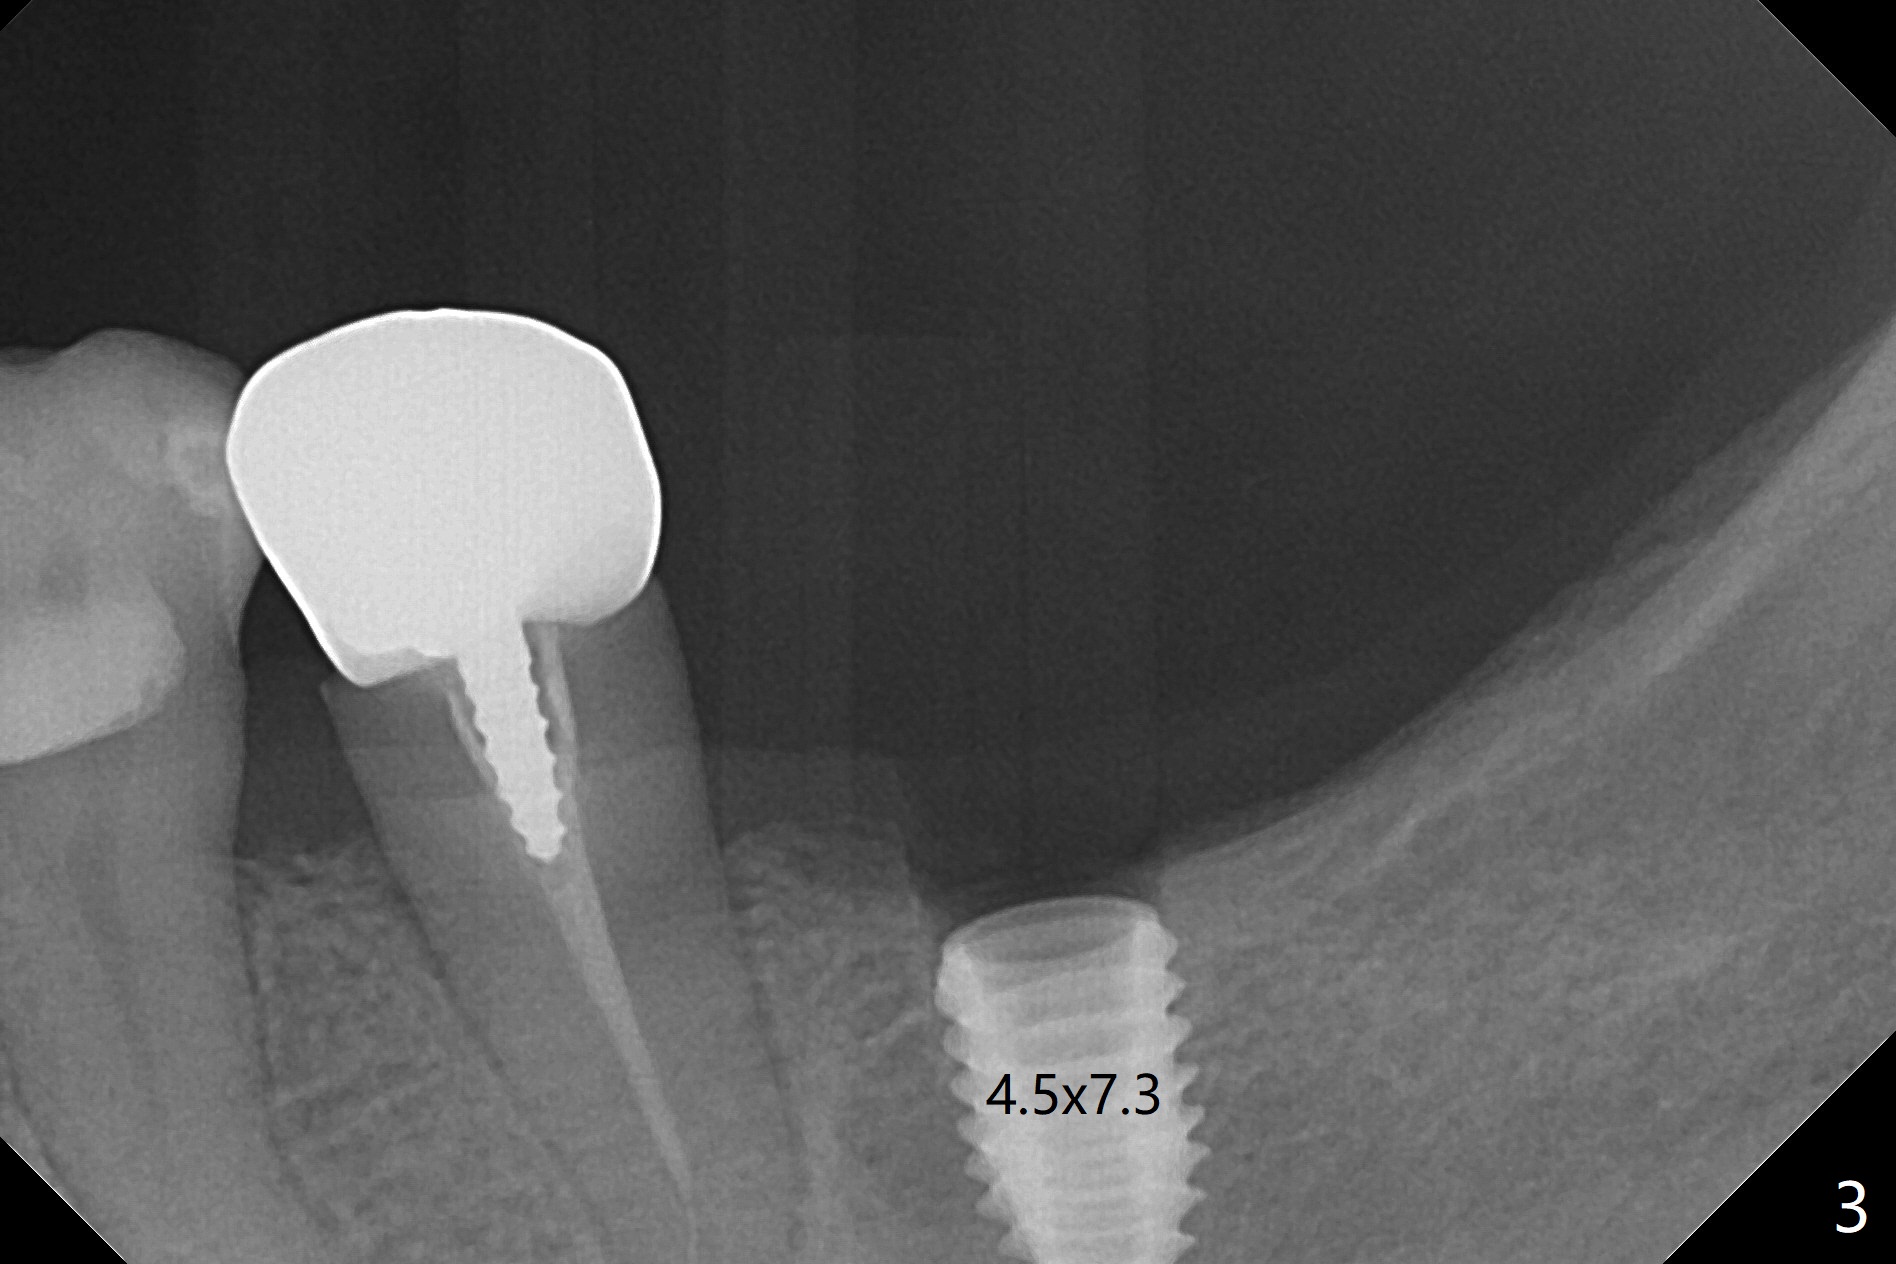

M

As a surgeon, I have never felt that my scalpel is as precise as media claims to be until guided surgery is introduced. The implants at #14 and 19 are placed as precisely as planned as well as painlessly and quickly (Fig.1-4). What else can we ask for? The gingiva around the healing abutment (5.5x3 mm) at #19 is erythematous (Fig.5). Later a longer healing abutment is used (Fig.6 (5.5x5 mm)). There is no bone loss 5 months or 7 months postop (Fig.6-9). The abutment screw is loose 3 months post cementation due to unfavorable crown/implant ratio (Fig.10); in fact the abutment is incompletely seated. Bicon implants will be in consideration to reduce screw loosening if implants are to be placed at #15 and 18. The abutment screw at #14 becomes loose 10 months post cementation; after retorque at #30 Ncm, the abutment is incompletely seated (Fig.11). It remains the same after use of 4.6 and 5.6 mm profile drills (Fig.12). A healing abutment is placed. When the patient returns, use planning kit and try to place a 5.2x5.5(2) cemented abutment. In fact it works (Fig.13). The crown at #19 is loose again 1 year 5 months post retightening. After removing crown/abutment, the mesial surface of the crown is heavily reduced. The crown/abutment is reseated to make sure that there is no proximal contact between the neighboring teeth (Fig.14 arrow). Because of tilt of the PA, it is difficult to tell the tightness of the contact between the implant and abutment, but the apical space is significantly reduced (*, as compared to Fig.10). Pick up impression is taken for porcelain addition occlusomesially. Two months later the patient returns for crown recementation. When the abutment is reseated with the repaired crown, the seating is incomplete (Fig.15). The abutment is completely seated when it is turned free hand with the flat surface of the abutment faces distal (Fig.16 D). The screw is torqued 20 Ncm before reimpression.